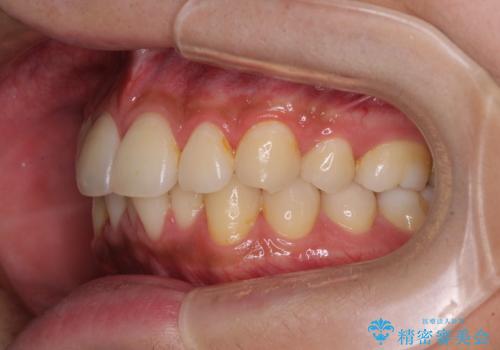

- 患者様

- 30代男性

- 矯正装置

- インビザライン・ライト

- 治療期間

- 9ヶ月

- 治療回数

- 5-10回

矯正治療後は、再度後戻りすることを極力回避するために、下顎前歯の舌側を細いワイヤーを用いて保定することとしました。